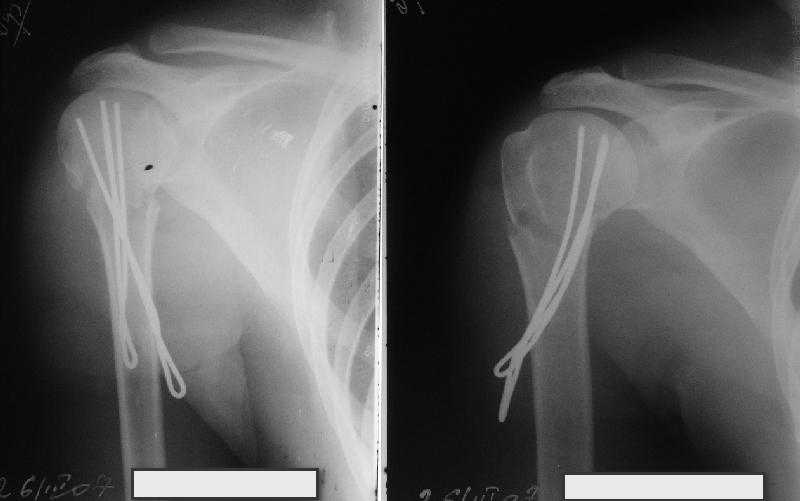

Очень даже неплохо получилось. Молодцы! Лучше чем на 3D "репозиции".

Все заняло 1 час. Собственно введение фиксаторов - минут 20.

Оставили в косынке, сразу разрешены маятникообразные движения в плечевом суставе. Дальше по ходу расскажу.

Все очень красиво получилось!

В приложении. Схема простая - по спице в каждый отломок, полукольцо проксимально, кольцо дистально, два телескопа. Как уже писал, ключевым моментом было введение спицы в плоскости диформации проксимального

оттдела плеча.